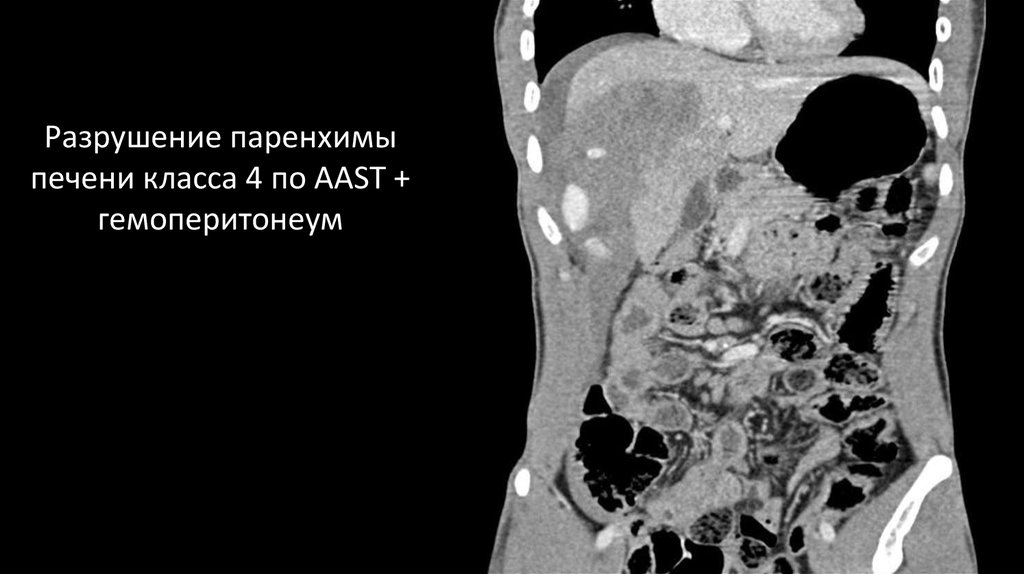

Разрушение паренхимы печени класса 4 по AAST + гемоперитонеум

30.

Разрушение паренхимы

печени класса 4 по AAST +

гемоперитонеум